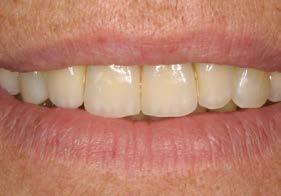

Figuras 2-3. Imágenes intraorales que evidencian pérdida ósea generalizada, extrusión de dientes anteriores y recesiones en todas las piezas presentes.

ósea vertical generalizada, defectos angulares en sectores posteriores y múltiples ausencias dentarias en ambos maxilares. La inspección intraoral mostró recesiones gingivales, exposición radicular y colapso del tercio anterior como consecuencia de migración dentaria y pérdida de soporte (Figura 1-3).

Figura 5. Aspecto intraoral posterior a las extracciones y a la ferulización de los dientes remanentes en el sector anterior superior, con el objetivo de mantener la estética durante la cicatrización. Las piezas conservadas fueron sometidas a tratamiento periodontal mediante raspado y alisado radicular, seguido de un programa de mantenimiento y control riguroso de placa en el postoperatorio.

caninos y premolares mediante tratamiento periodontal intensivo. Esta decisión favoreció la integración funcional de dientes e implantes, manteniendo la propiocepción y mejorando el control de posibles sobrecargas funcionales como el bruxismo.22-24

La paciente continúa en seguimiento. A los 8 años, la estabilidad de los tejidos duros y blandos, así como la estética de la rehabilitación, era completa (Figura 9-11). A los 12 años se observó

una buena progresión del tratamiento, sin cambios reseñables (Figura 1214). A los 20 años de seguimiento se constató una evolución estable, sin pérdida ósea en dientes ni implantes, y con buena salud de los tejidos periimplantarios (Figura 15-17).